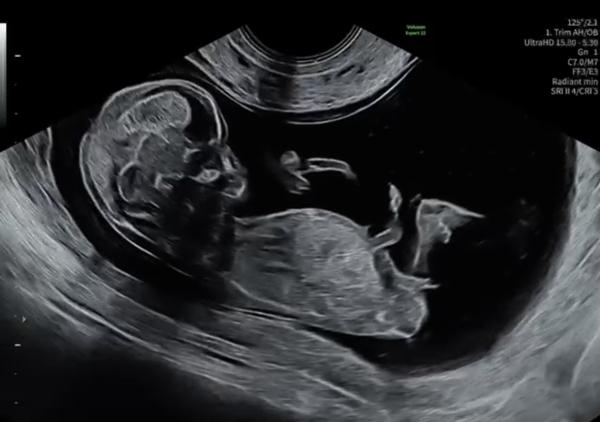

Hallo, kennt sich jemand gut mit der Nub Theorie aus und erkennt möglicherweise das Geschlecht des Babys?🙈

Bild zu Junge oder Mädchen - Schwanger - wer noch? Rund um die Schwangerschaft

Ich glaube Junge.  Herzlichen Glückwunsch